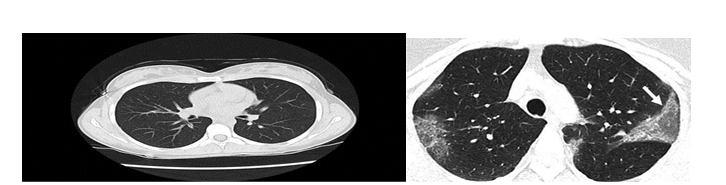

Figure 1Coronavirus and pro physician chest X-ray pictures Figure 2Coronavirus and Non Corona virus adolescents' chest Tomography pictures

According to the Centers for Disease Control and Planning, Even if a chest CT or X-ray shows COVID-19, its only definitive technique of diagnostic is the viral screening (CDC). And endeavor is the first step in creating a tool that verifies or provides further details regarding the present disease through viral investigation. The greatest result to have is achieved by VGG-19 (spatial Geography Group), which classifies pulmonary symptoms with a highest score of 100 percent. The normal class did well, though the COVID-19 classes have had minor issues. Categorization issues despite strong results. So far, in the COVID-19 class, this model has produced the greatest and most regular outcomes.